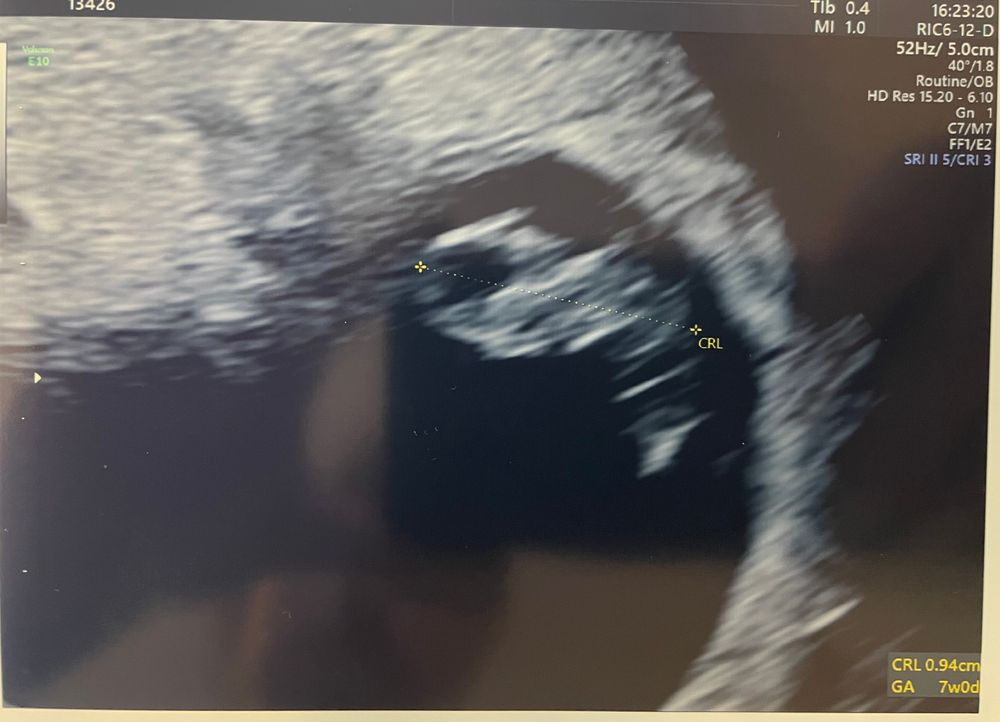

Срок 7+1 недель🤞❤️🤞

Результаты УЗИДевочки ❤️ Сегодня была на узи, наконец-то я услышала сердечко нашего малыша❤️❤️❤️В прошлый раз Ре только сердечко видела.

ЖМ 3,3 мм

КТР 9,6 мм

ЧСС 160 ударов

И собственно сам малыш 😍